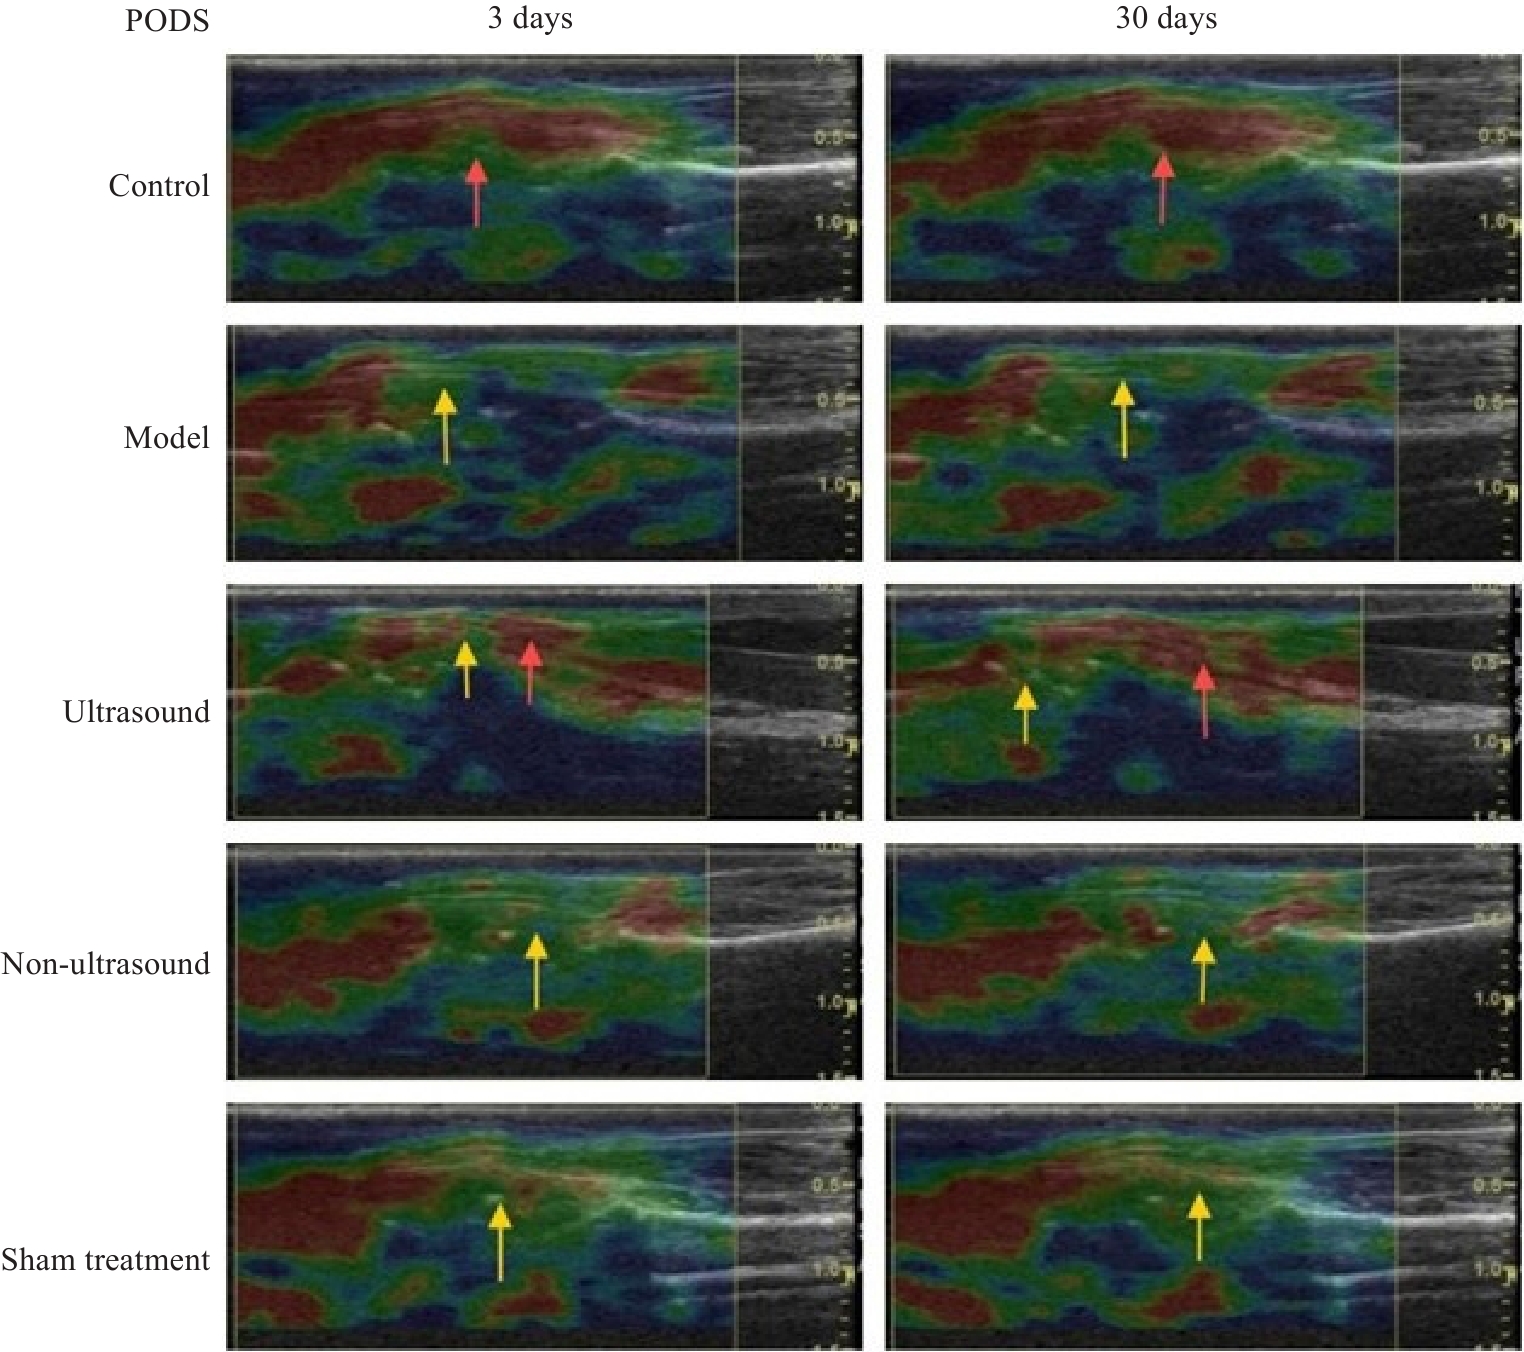

Fig.3 Ultrasound elastography of the TCL of the rabbits in the 5 groups. PODS:Postoperative days. Red arrow: Softer tissue; Yellow arrow: Firmer tissue.